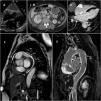

A 64-year-old woman was referred for evaluation of constitutional symptoms, dyspnea and right heart failure. There was a high level of inflammatory markers in the blood test, so blood culture and image tests were performed to rule out endocarditis. Echocardiography did not show valve disease and revealed normal systolic function and a mass at the auriculoventricular sulcus (Figure 1A). Thoracic-abdominal computed tomography ruled out inflammatory and neoplastic diseases, showing the heart mass, perirenal and retroperitoneal fibrosis spreading to pararenal and paraaortic space (Figure 1B) and areas of bone sclerosis in pelvis and vertebrae. Magnetic resonance imaging was performed afterwards. Cardiac cine-balanced fast field echo shows the cardiac mass as an extensive hypointense tissue surrounding the right atrium (Figure 1C) with intense enhancement after intravenous administration of contrast at the inversion-recovery sequences (Figure 1D and E). Intense enhancement was also seen in all aortic wall, supra-aortic trunks, visceral and pulmonary arteries suggesting extensive vascular adventitial fibrosis (Figure 1E). Finally, a retroperitoneal biopsy showed chronic IgG4-lymphoplasmacytic inflammation with a xanthogranulomatous component. In the molecular test, a specific mutation in the BRAF gene was found pointing to Erdheim-Chester disease as the diagnosis.

A: Ecocardiography showing mass at the auriculoventricular sulcus; B: Perirenal and retroperitoneal fibrosis seen in computed tomography; C: Magnetic resonance imaging (MRI) showing cardiac mass and hypointense tissue surrounding right atrium; D and E: MRI, inversion-recovery sequences showing intense enhancement in heart mass and aortic wall.